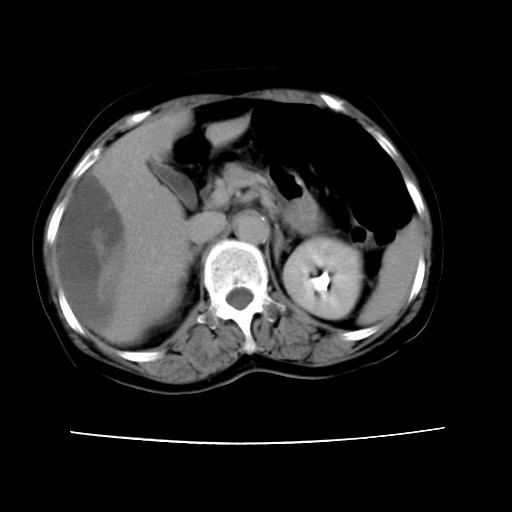

2008-11-10ct平扫(其间去中山医院诊治未行特殊治疗)

2008-11-10ct平扫见并肝内、血膜下血肿基本吸收,肝内低密度灶缩小。此时再做增强ct应有显着意义。对患者/医者都好!

从平扫+增强及治疗后复查片,病变明显缩小,不考虑肝癌出血可能,还是考虑为良性病变可能性大;单纯血肿并包膜下积液吧,病变强化没法解释,肝血管破裂出血吧,增强不符合典型血管瘤的表现,良性肿瘤破裂出血吧,复查片看来好像也不太支持(没做强化也不太好说)。本人还是考虑单纯肝内血肿并包膜下积液,强化是不是血管有外渗。

患者自6月至11月,如果是肝癌,没有经过特殊治疗,想必应该会有所进展吧,而不是ct所见,反而似有病灶减小的趋势。建议增强。

病变破裂出血应首先考虑,病变性质即可能是恶性也可能是良性,楼主说患者到上级医院检查未见癌细胞,以良性可能性大,首先考虑腺瘤破裂出血可能。

追问病史,患者有过度用力病史,当时立即感腹痛;所以还考虑肝破裂可能性大。